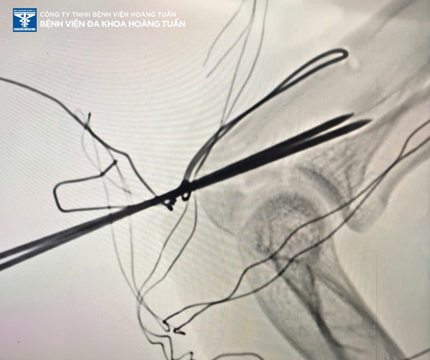

Điều trị phẫu thuật kết hợp gãy mỏm khuỷu:

- Phẫu thuật kết hợp khớp khủy tay được chỉ định cho gãy di lệch nhiều, gãy hở.

- Phương tiện được sử dụng để kết hợp xương là: Đinh và chỉ thép hoặc nẹp vít.

Sau điều trị, nhờ sự cố gắng của tập thể các Bác sĩ, nhân viên y tế tại Bệnh viện Đa khoa Hoàng Tuấn bệnh nhân giảm đau, cải thiệu về tầm vận động và thẩm mỹ. Đây cũng là niềm vui của phía Bệnh viện Đa khoa Hoàng Tuấn khi có thể giúp các bệnh nhân điều trị ổn định, phục hồi tốt nhất trong thời gian ngắn.